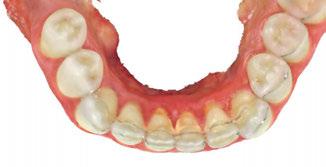

Figures 1A and 1B: Adolescent with anterior open bite: Orthognathic surgery unnecessary post-myofunctional therapy. 1A. Pre-myofunctional therapy: The bite only touched on the back molars, yet the patient had already gone through full braces. The original orthodontist recommended orthognathic surgery to close the bite. The patient was referred for a second opinion. The second orthodontist recognized the tongue thrust and referred the patient for myofunctional therapy but made no guarantees that the patient would not need jaw surgery. 1B. Post-myofunctional therapy: After 2.5 years of braces and myofunctional therapy, the orthodontist gave the patient the good news that jaw surgery would not be necessary. The myofunctional therapy allowed the orthodontist to close the bite once the tongue pressure was removed from between the teeth

Figures 2A and 2B: Open bite corrected with myofunctional therapy. 2A. Pre-myofunctional therapy: This patient was in braces for 3 years with no success at closing the open bite. 2B. Post-myofunctional therapy: After 5 months of myofunctional therapy to address the mouth breathing and tongue thrust, the open bite closed

Figures 3A and 3B: 3A. Pre-myofunctional therapy: Anterior open bite caused of soft tissue dysfunction including incorrect lingual rest posture and tongue thrust. 3B. Post-myofunctional therapy: 4 years after the start of myofunctional therapy with no orthodontic treatment, and the open bite closed. By taking the tongue pressure off of the teeth in OMT, the occlusion was able to normalize. The orthodontist feels the patient does not need braces

Figures 4A and 4B: Unilateral open bite developed later in life. 4A. This patient’s unilateral open bite was due to a change in muscle function, as after a left root canal, the patient began to only chew on the right side. This chewing pattern changed the muscle balance as the patient continually spread the right side of the tongue to push food onto the teeth. There was no orthodontic progress, and the patient was referred for orofacial myofunctional therapy. 4B. OMT restored muscle development, resting tongue posture, correct chewing function, and correct swallowing. In 5 months, the patient was debanded